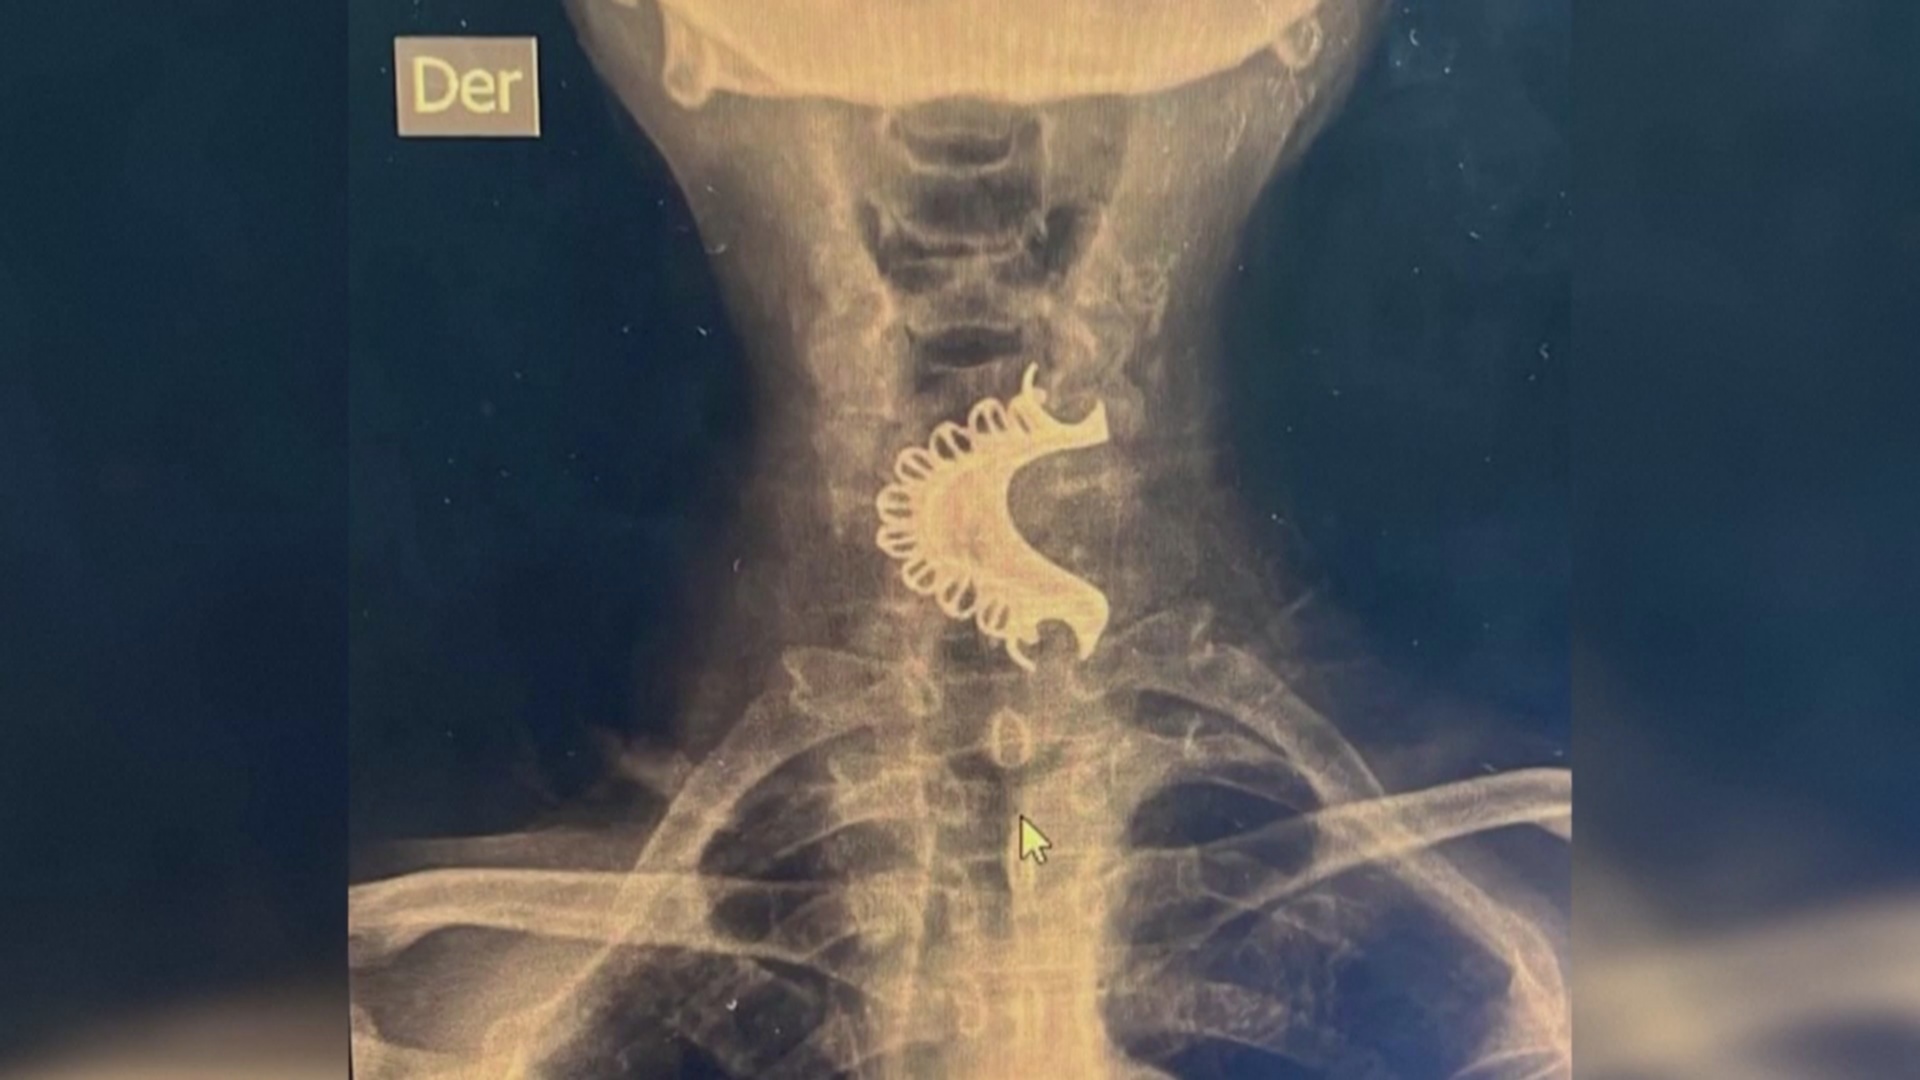

В больнице сделали рентген и увидели в горле зубной протез. На операцию пациента перевели в специализированную клинику.